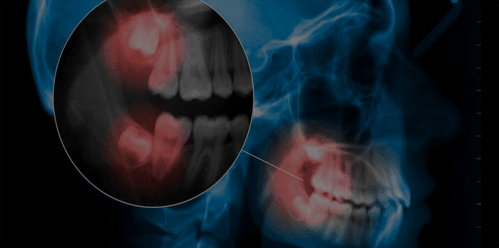

Módulo 8 – Cirurgia de Terceiros Molares

• Classificação e planejamento cirúrgico

• Técnica de acesso, osteotomia e odontosecção

• Prática: cirurgia de terceiros molares inclusos

Módulo 9 – Planejamento Radiográfico e Documentação

• Interpretação de panorâmicas e tomografias

• Planejamento cirúrgico com base em imagem

• Prática: planejamento e execução de casos com suporte radiográfico